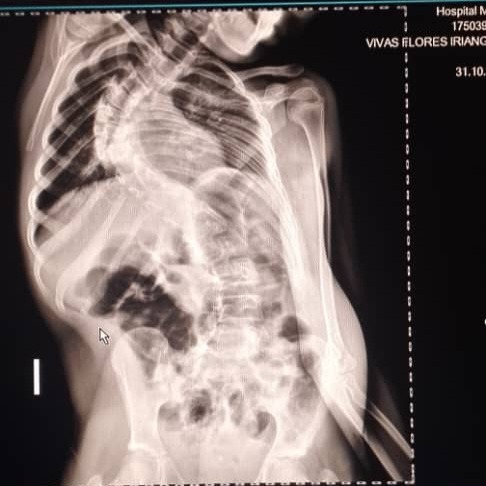

Hola me llamo iriangela y por medio de mi familiar que logró crear esta cuenta estamos recaudando fondos para mi operación, como dicen mis informes médicos padezco de escoliosis asociada a mi síndrome lo cual afecta mi columna vertebral y compromete mi calidad de vida, mis padres no cuenta con los recursos necesarios para dicha operación que se sugiere de emergencia también debo viajar a caracas y debemos cubrir gastos de comida hospedaje y transporte ya que somos del estado tachira sin familia en caracas cualquier granito de arena seria de gran ayuda para mi, de antemano gracias Dios les bendiga!